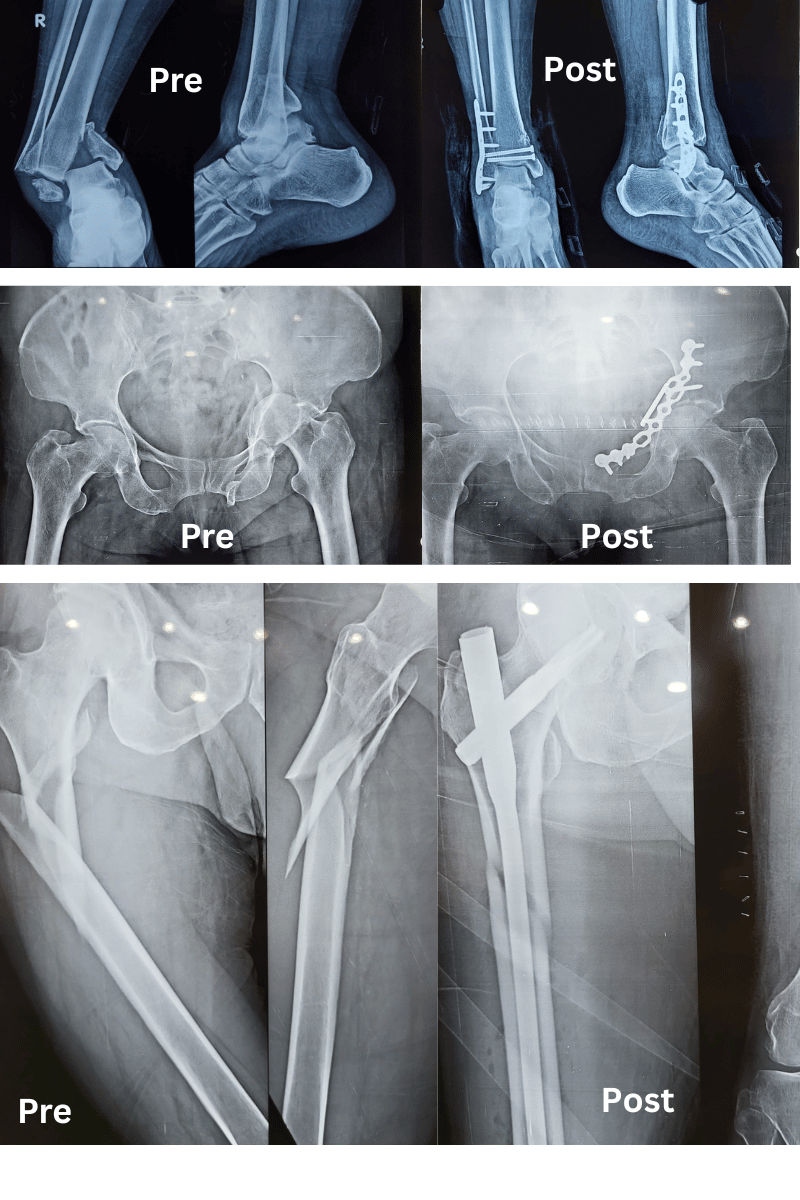

Sivam Hospital – Advanced Trauma Care In Chennai

At Sivam Hospital, we provide 24/7 emergency and trauma care with highly skilled doctors, advanced equipment, and immediate response. Our trauma center specializes in critical injury management, accident care, emergency surgery, and life-saving treatment.

Our expert trauma team provides comprehensive fracture and injury management with advanced techniques and personalized care.

Simple Fractures – Treated effectively with splinting or plaster of paris application 24X7

Compound Fractures – Specialized care to prevent infection and restore function.

Major Fractures – Multimodal treatment to stabilise the patient immediately and team work to stabilise the fractures and other associated injuries (Head injuries, abdominal injuries)